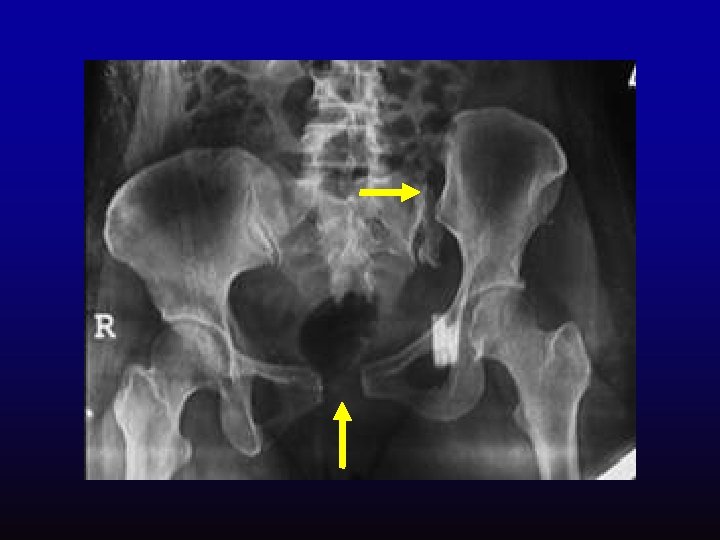

Acute extradural midline shift ventricle compression

Acute subdural Compression and shift